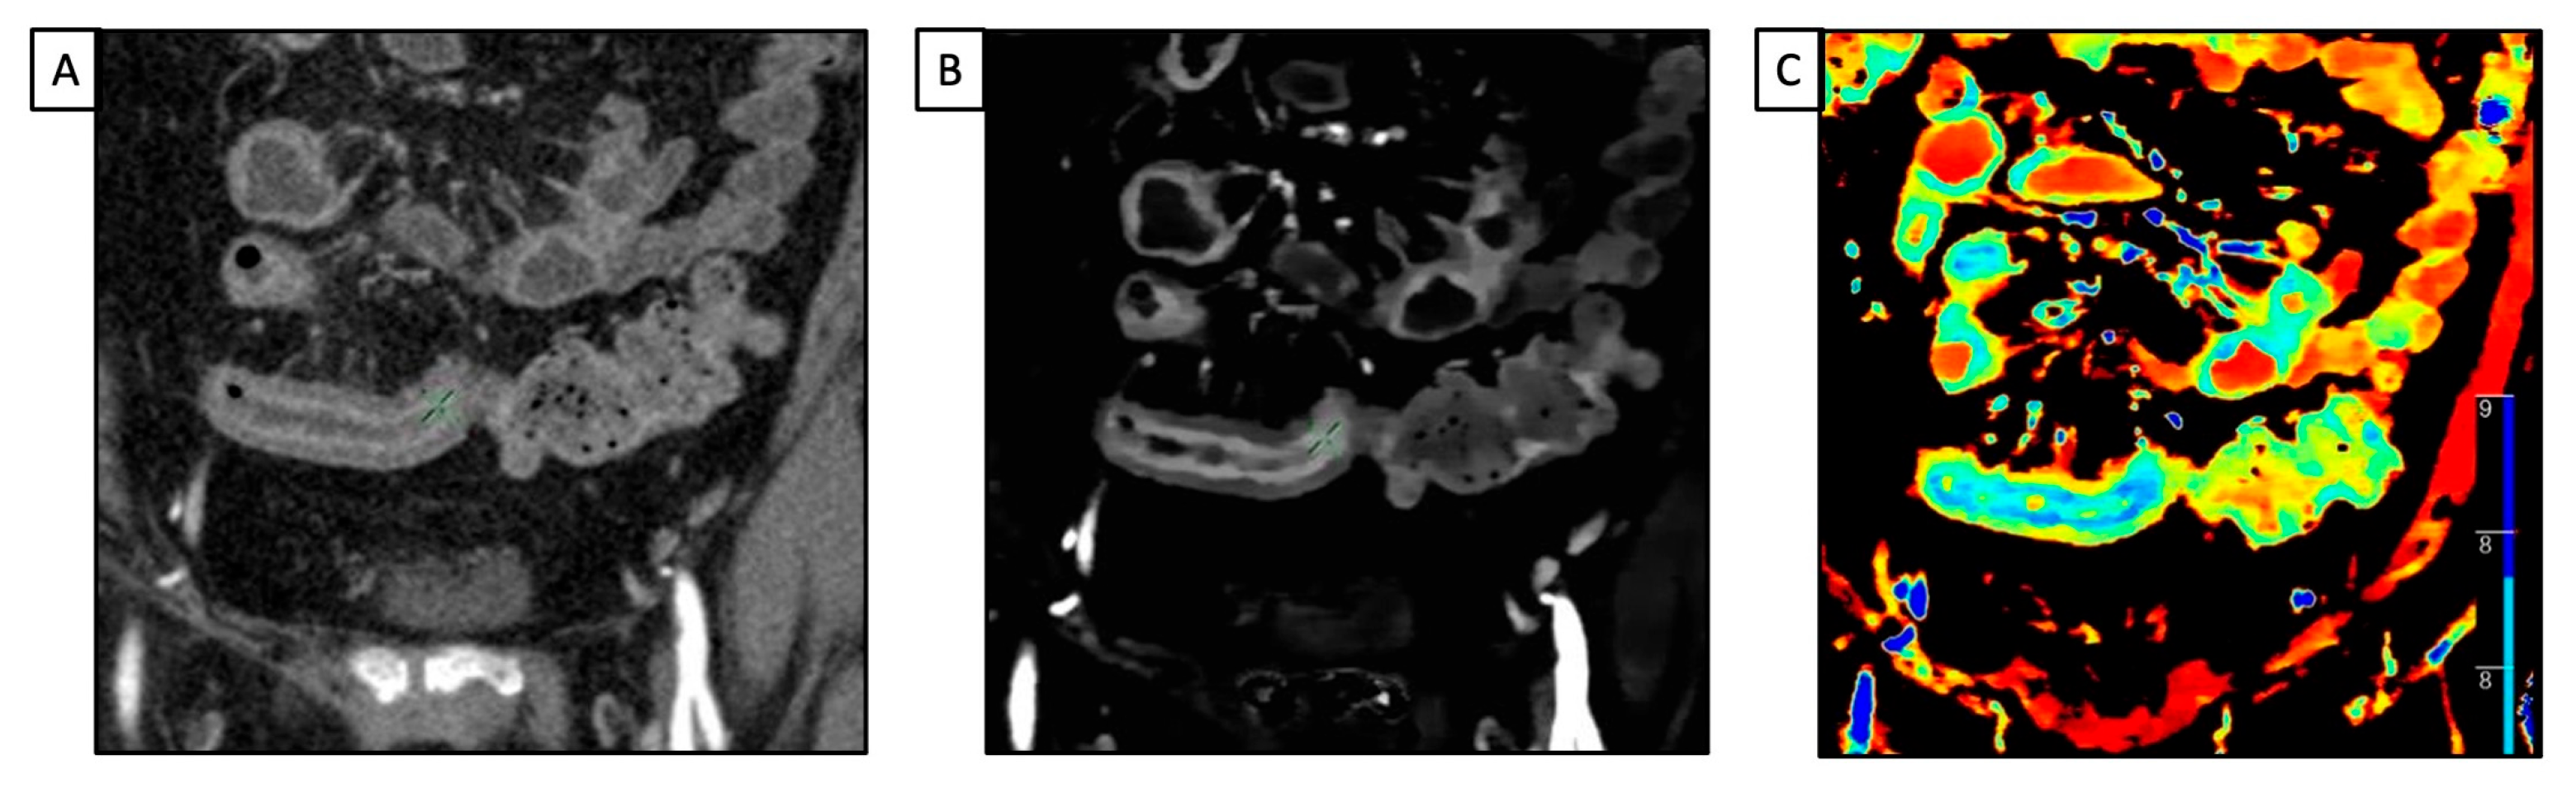

In CT diagnosis, gallbladder stones are indicated directly via high-density or low-density stones and indirectly via the dilation of the intrahepatic biliary duct, left and right hepatic ducts, biliary duct, and gallbladder [30]. Based on density, gallbladder stones are classified into high-, iso-, low-, and mixed-density stones, relative to the density of the surrounding bile. Conventional SECT has high accuracy in diagnosing high-density or low-density gallbladder stones [31]. However, it is challenging to diagnose iso-density stones, such as those made of cholesterol, due to their similar attenuation value with the bile (Figure 2).

Figure 2.

A 42 y-o patient with right upper pain underwent abdominal CT with a final diagnosis of cholecystitis. (A) Conventional CT image acquired after intravenous contrast media injection shows diffuse thickening of the gallbladder wall, without evidence of any calcific stone; (B) low mono-energetic map shows a hypoattenuating round stone, due to cholesteric composition; (C) opposite that, the high mono-energetic map demonstrates the hyperattenuating mass consistent with the cholesteric gallstone; (D) the Z-effective map allows us to better define the different structures of the images via the different atomic values of the gallbladder: blue (contrast agent), red (lipid content), and green (fluid).